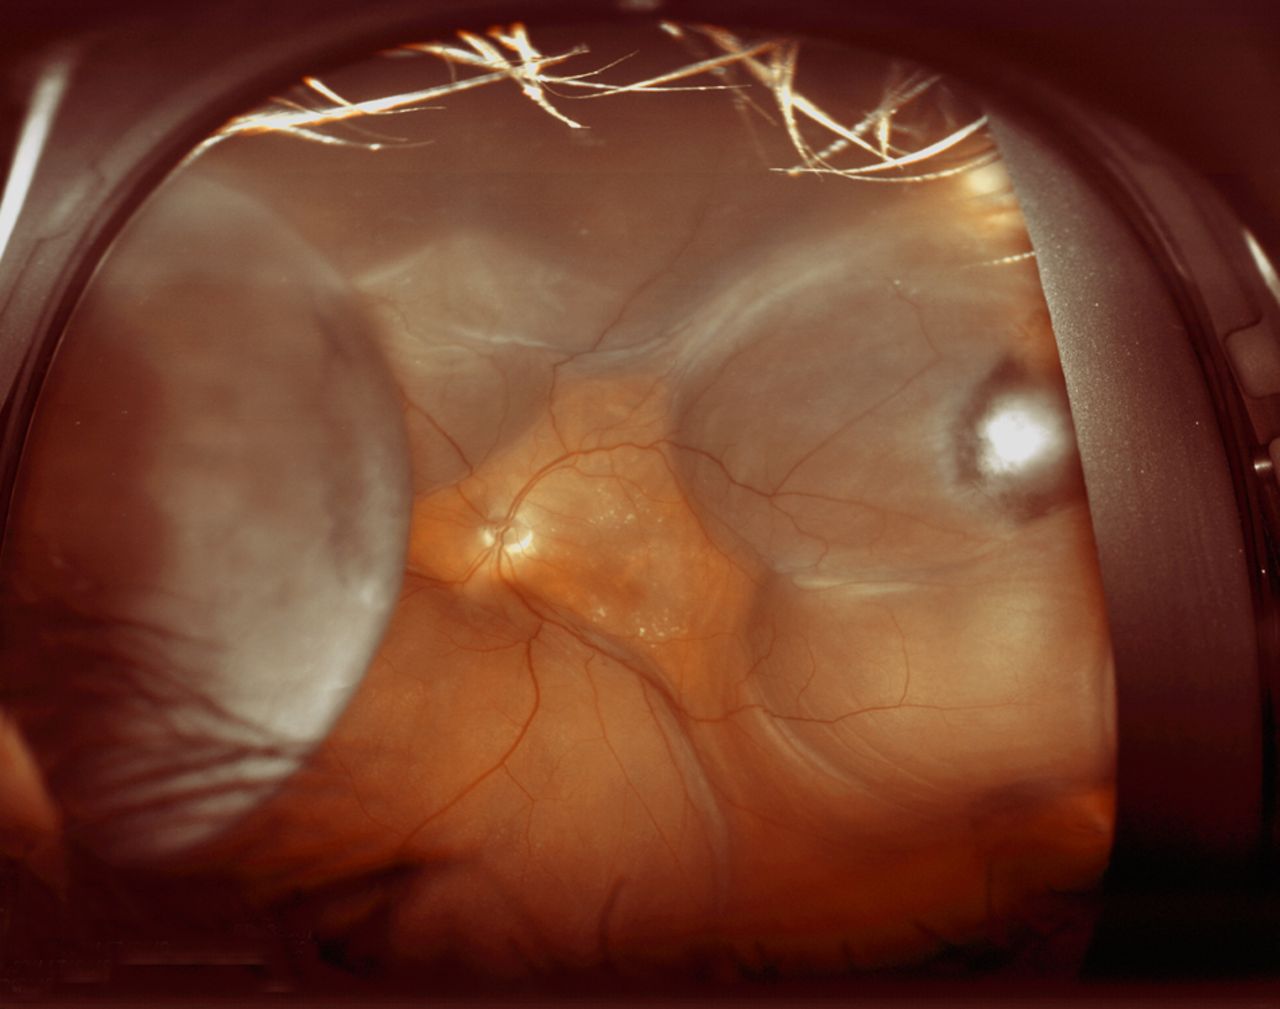

<지연성 맥락막 상강출혈, Delayed Suprachoirdal hmr>

흔하지는 앟으나 약 2%의 발생률을 보이는 심각한 합병증으로,

수술후 1주일째 정도에 발생하며, 맥락막과 공막사이에 출혈이 고임으로 인해,

후방압력이 증가되어,

홍채-수정체 격막의 전방이동(lens-iris diaphragm anterior shift)이 발생하며,

전방이 소실되면서, 안압이 증가된 소견을 보입니다.

보통 2주 정도 기다려보면 고여있는 혈액이 응고되다가 다시 용해되게되는데,

이때 수술적 치료를 통해 공막절개를 하여, 고여있는 출혈을 제거할수 있습니다.

하지만 수술적 치료에도 예후가 불량하며,

망막박리가 동반되거나, 광범위한 맥락막상강출혈이 있는 경우 예후가 매우 불량합니다.